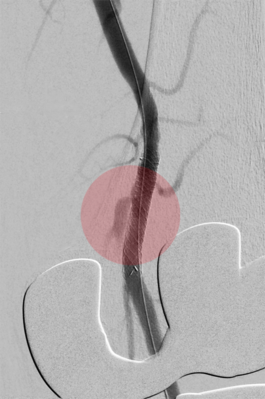

6. Fibrinolyse – medikamentöses Auflösen von Blutgerinnseln

Gefäßverschließende Blutgerinnsel können auch durch Medikamente aufgelöst werden, um den Blutfluss wiederherzustellen. Damit dieses Medikament sicher und effektiv wirken kann, wird es über einen Katheter direkt zum Verschluss gebracht. Das erfolgt über eine langsame mehrstündige Gabe. Zur Verbesserung der Wirkung kann durch Spezialkatheter das Medikament mit Hilfe von Schallwellen in das Blutgerinnsel transportiert werden.